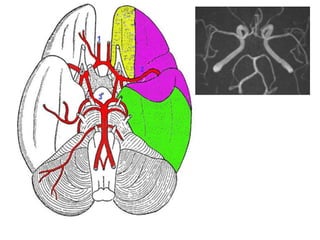

• Du à une occlusion d’une branche ou

d’une artère à destination cérébrale

• Mécanisme embolique ou

hémodynamique

• Clinique en fonction du territoire

vasculaire

– Infarctus sylvien superficiel,

profond ou total

– Infarctus cérébral antérieur

– Infarctus cérébral postérieur

– Infarctus dans le territoire de la

PICA etc